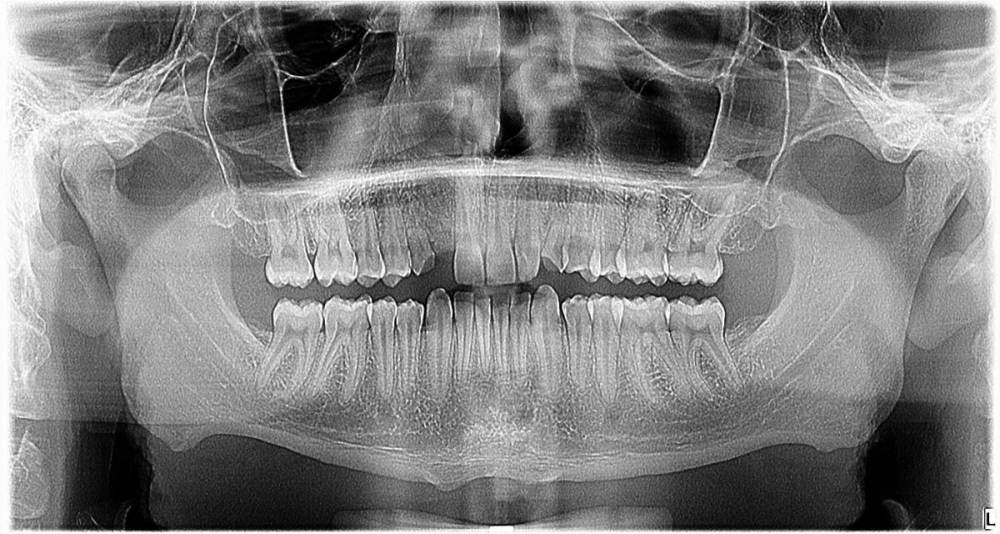

smikvarnik Опубликовано 12 июня, 2023 Поделиться Опубликовано 12 июня, 2023 (изменено) Здравствуйте, проблема следующая 25 лет, пол М У меня с детства аномалии(нет корней на 3х зубах), одна двойка справа молочная + тройки молочные. Двойка выпала и хожу с дыркой уже лет 10, также зона улыбки кривовата и есть промежуток между однерками тройки молочные маленькие но держатся, все хорошо. Самая главная проблема по которой мне многие отказывали в реставрации только зоны улыбки, это прикус. у меня глубокий прикус с детства. Ортодонты говорят что нужно носить брекеты 2-3 года, и только после этого имплантация либо коронки с мостами. Но пару ортопедов предложили мне сточить все верхние зубы(все жевательные зубы в отличном состоянии, передние так себе, уже немного сточены из за прикуса). Говорят что если поставить без исправления прикуса - я просто выбью коронки или импланты, нагрузка будет не такая какая должна быть Пробовал также ходить с капой чтобы поднять прикус - результатов нет. некоторые врачи отказывали даже в лечении брекетами, говоря что ситуация сложная. Также зубы для моего возраста маленькие, по сравнению с другими людьми Говорят что если сделать коронки на верхней челюсти, можно таким образом исправить прикус+сделать улыбку без ортодонтии. но также возможно потребуется сточить немного зубов на нижней(не уточнял какие) Коронки из диоксида циркония как вы считаете, это нормальный вариант, или так себе? у меня психологический комплекс из за зубов и еще 2-3 года ходить с брекетами и дырками честно говоря так себе идея. Какие есть минусы и опасности у такого варианта, и как с вашей точки зрения, как докторов, этот вариант оценивается? Насколько это целесообразно? Спасибо за помощь заранее, очень жду ответ, каждый день волнует эта тема Изменено 12 июня, 2023 пользователем smikvarnik Ссылка на комментарий

smikvarnik Опубликовано 13 июня, 2023 Автор Поделиться Опубликовано 13 июня, 2023 здравствуйте, не видел! исправляю еще также есть фото лица и самих зубов, как попросите так и сфоткаю. также есть КТ ВЧ и НЧ Ссылка на комментарий

smikvarnik Опубликовано 13 июня, 2023 Автор Поделиться Опубликовано 13 июня, 2023 если неудобно - другой ракурс, чтоб голову не поворачивать Ссылка на комментарий

smikvarnik Опубликовано 13 июня, 2023 Автор Поделиться Опубликовано 13 июня, 2023 также ситуация во рту, и с прикусом. молочные зубы выделил. извините за флуд) Ссылка на комментарий